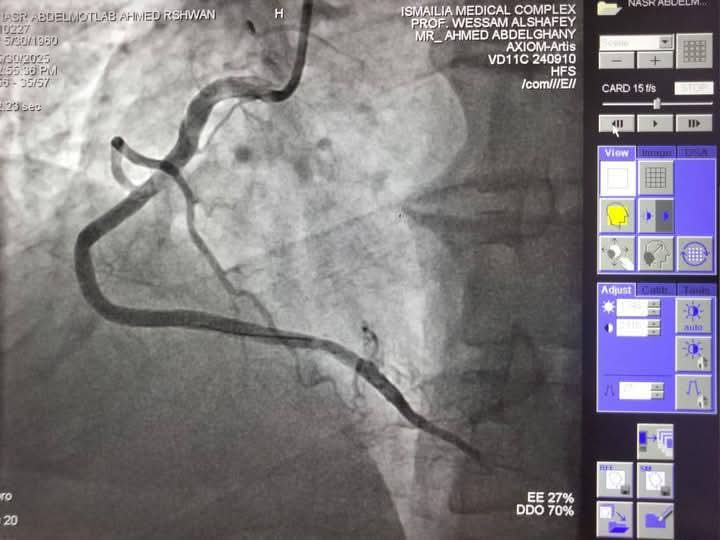

تمكن فريق قسطرة القلب في مجمع الإسماعيلية الطبي من إنهاء معاناة حالتين متوسط عمرهما 60 عامًا، كانتا تعانيان من أعراض متكررة لأزمات قلبية، بعد إجراء قسـطرة تشخيصية.

الحالتان كانتا تعانيان من انسداد في الشريان التاجي

وتبين وجود انسداد كلي مزمن في الشريان التاجي CTO-RCA، مما استدعى التدخل العاجل نظرًا لتعقيد وخطورة الحالات، وتحت إشراف خبير قسطرة الشرايين التاجية المعقدة بمجمع الإسماعيلية الطبي، وهما الأستاذ الدكتور وسام الدين الشافعي، تم إجراء قسطرة علاجية ناجحة لكلا الحالتين، حيث تم استخدام تقنيات حديثة تشمل توسيع الشرايين بالبالونات الدوائية وتركيب دعامتين دوائيتين للحالة الأولى، وثلاث دعامات للحالة الثانية.